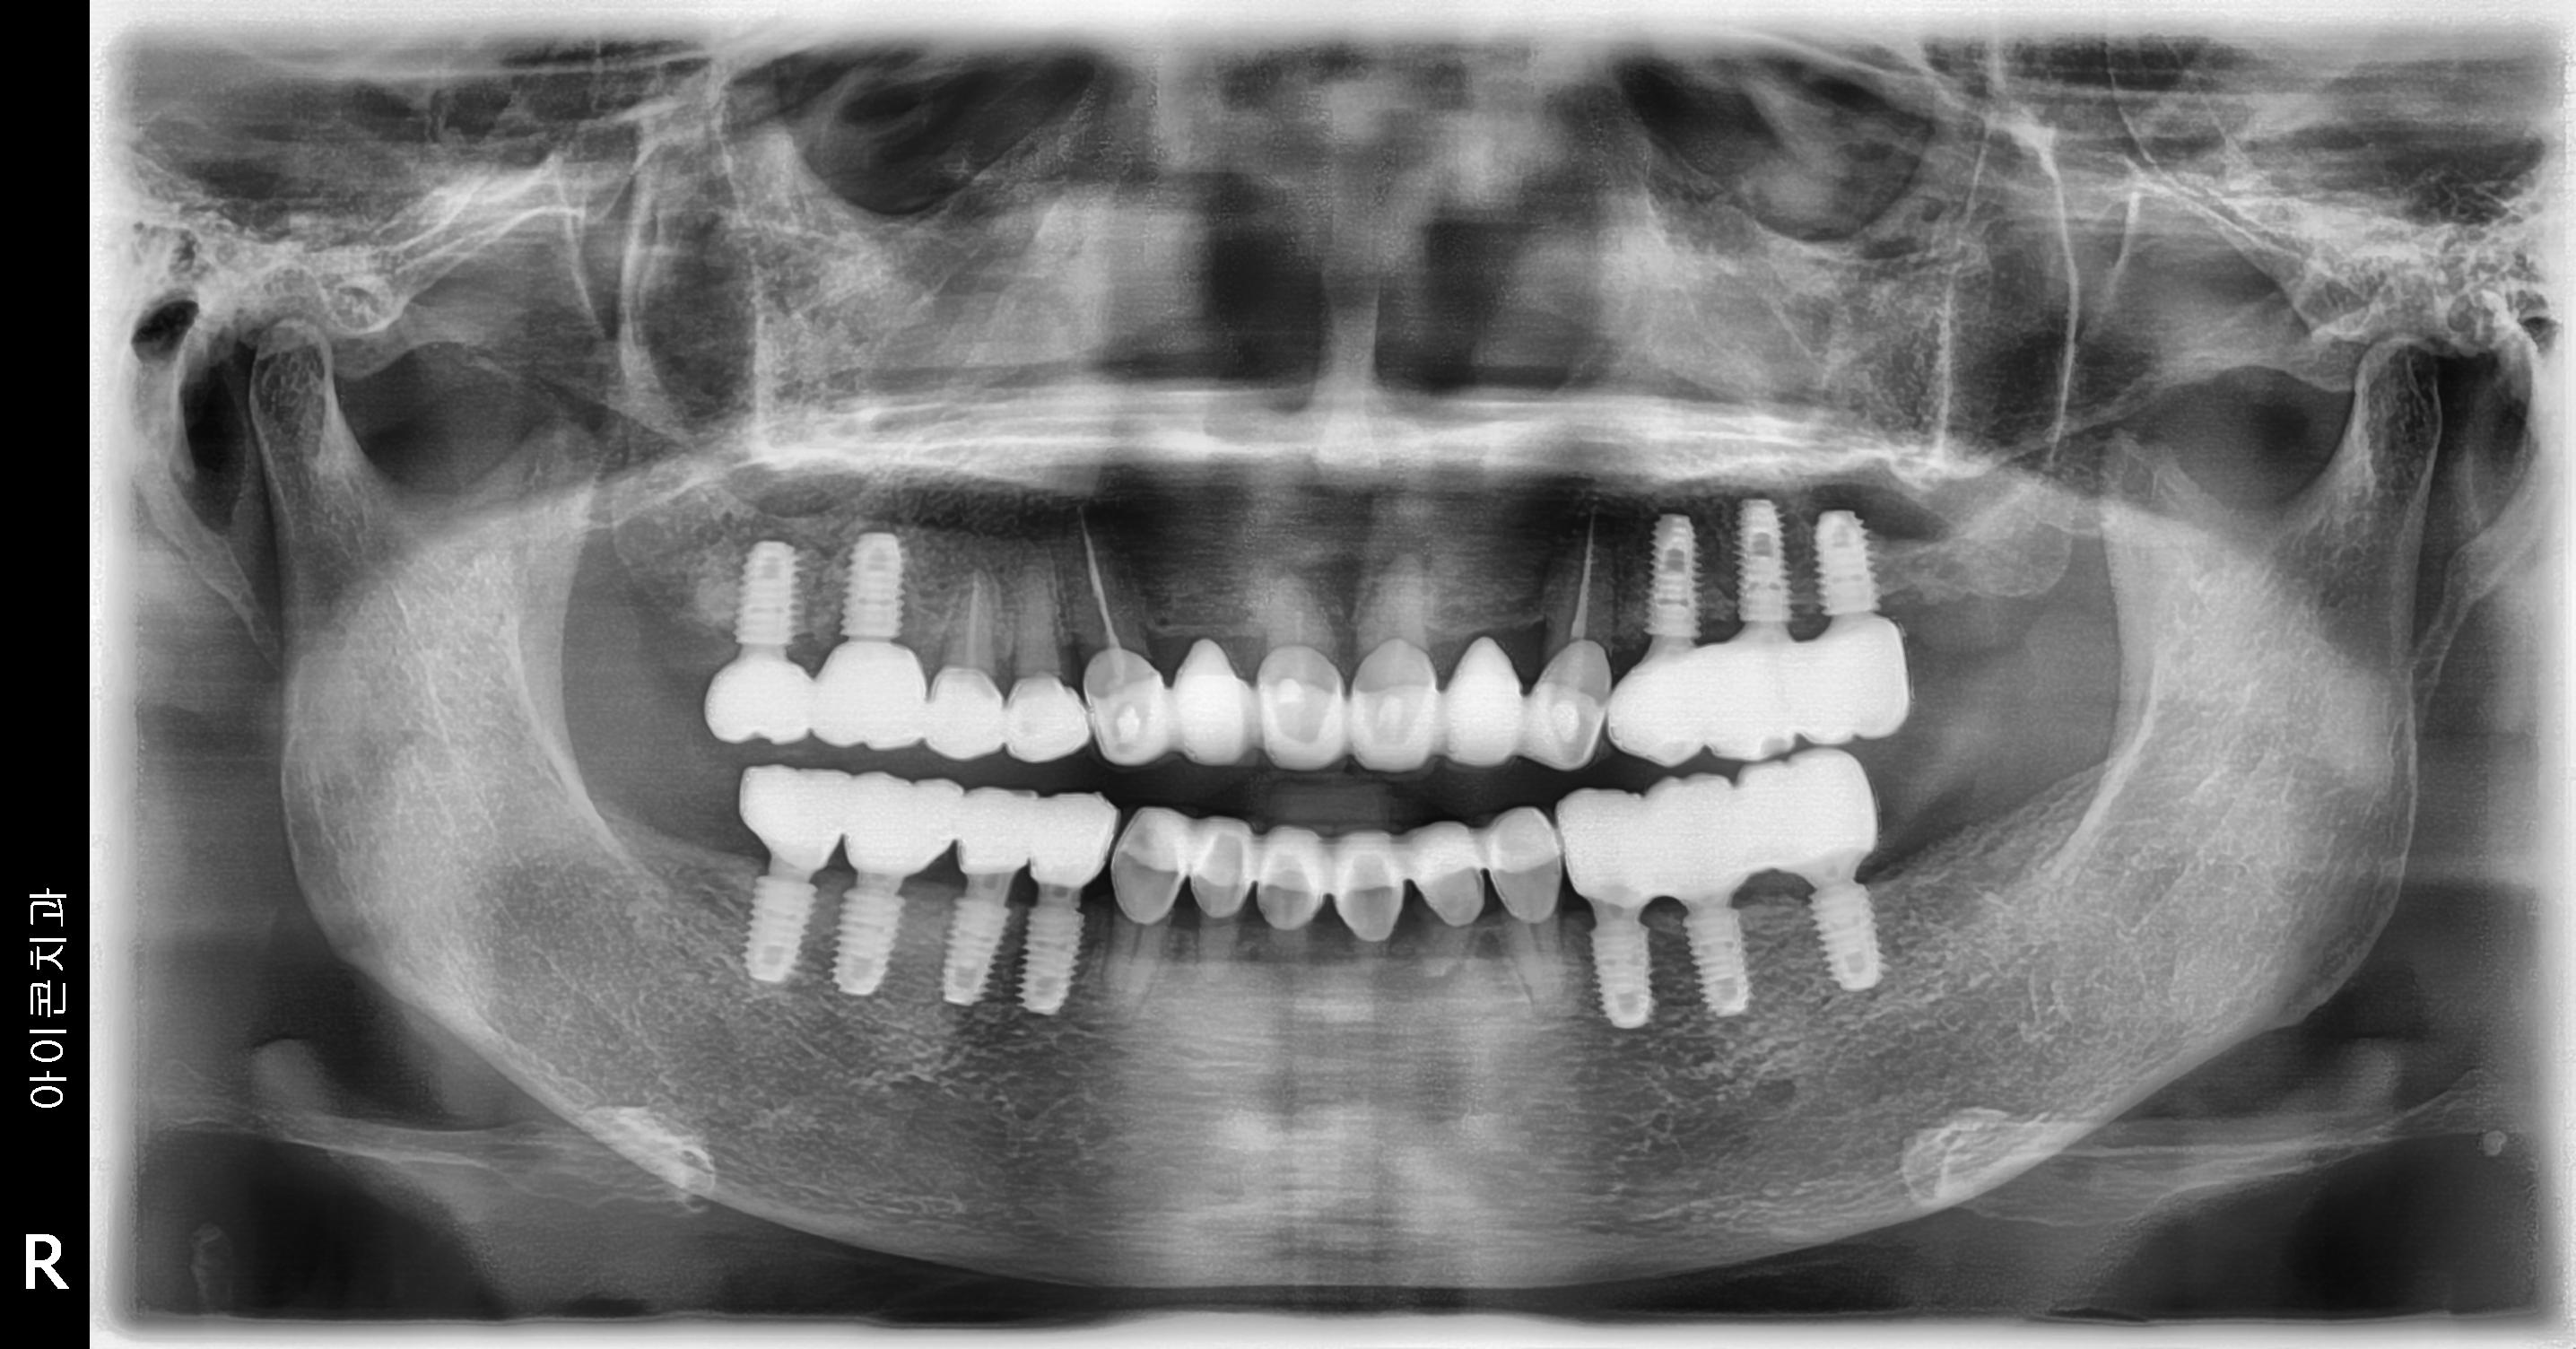

수술 전

수술 후

좌측 임플란트 흔들림 재수술 사례

전후사진